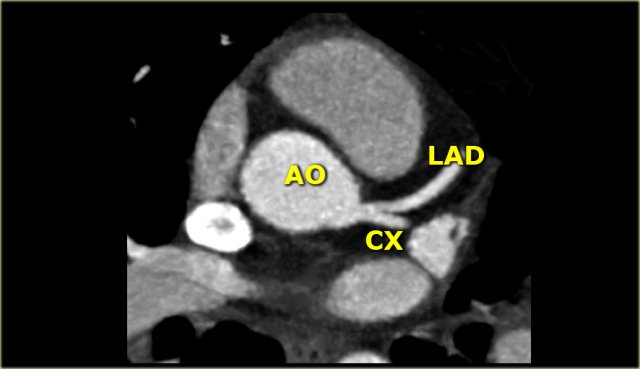

The LCA divides almost immediately into the circumflex artery (Cx) and left anterior descending artery (LAD).

On the left an axial CT-image.

The LCA travels between the right ventricle outflow tract anteriorly and the left atrium posteriorly and divides into LAD and Cx.

On the image on the left we see the left main artery dividing into

- Cx with obtuse marginal branch (OM)

- LAD with diagonal branches (DB)

Circumflex (Cx)

The Cx lies in the left AV groove between the left atrium and left ventricle and supplies the vessels of the lateral wall of the left ventricle.

These vessels are known as obtuse marginals (M1, M2...), because they supply the lateral margin of the left ventricle and branch off with an obtuse angle.

In most cases the Cx ends as an obtuse marginal branch, but 10% of patients have a left dominant circulation in which the Cx also supplies the posterior descending artery (PDA).

Mnemonic: Marginal branches arise from the Cx and supply the lateral Margin of the left ventricle.